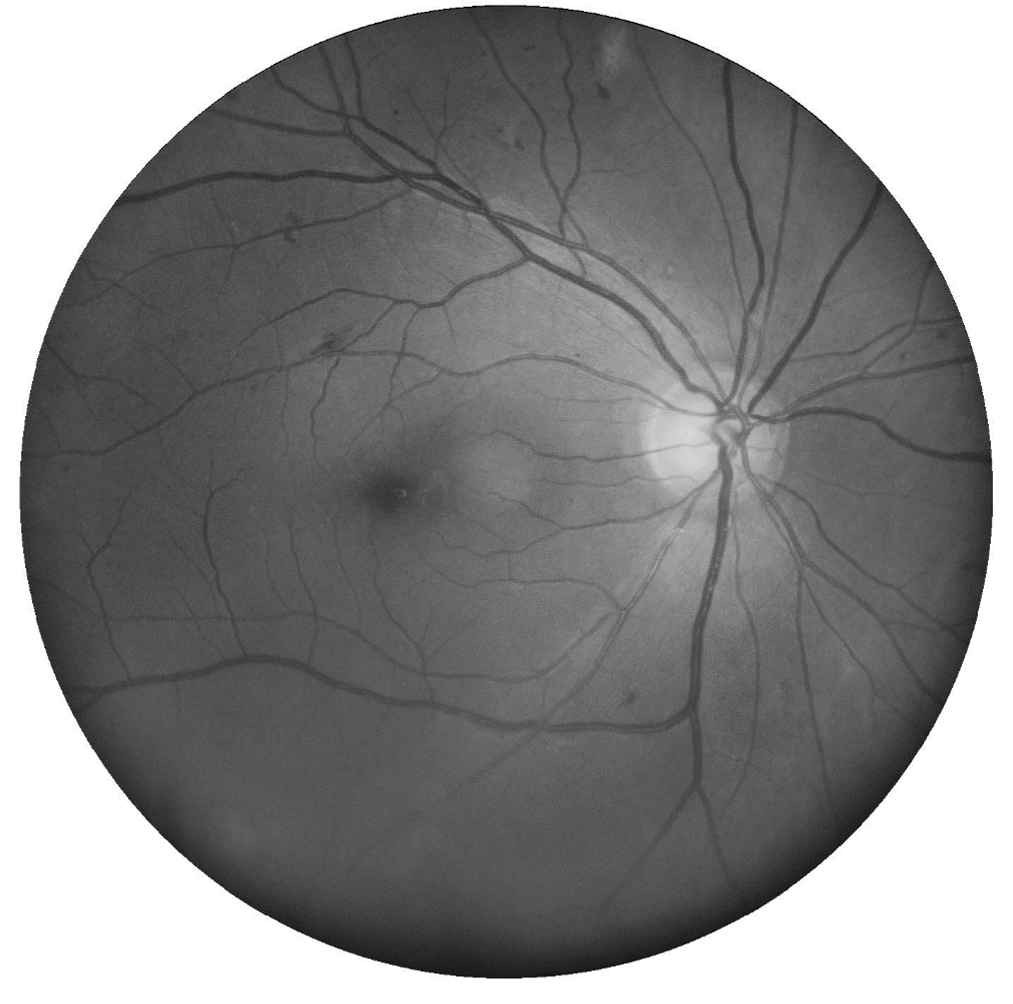

Microaneurysms are the earliest clinical sign of DR. They are outpouchings of the capillary wall, due to pericyte loss, which can rupture and leak leading to intraretinal haemorrhage, oedema or hard exudate.

Clinically, they appear as isolated, round red dots of varying size which can resolve spontaneously. They may be undetectable on OCT or, if visible, typically appear as small round or oval lesions, originating from either the superficial or deep capillary plexi , fully or partially capsulated in 56% of cases.

Fundus photo, red-free image, OCT line scan, OCT angiography - Microaneurysm